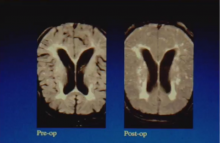

Jonathan Anderson of Hammersmith Hospital in London, UK, argues that surgeons should be interested in the effect that cardiopulmonary bypass has on a patient. He makes the case that even though cardiopulmonary bypass is safe, it should be continually improved to reduce its negative effects on the patient. Dr Anderson presents a brief history of early techniques for extracorporeal circulation and discusses more recent advances in minimally invasive circuits.